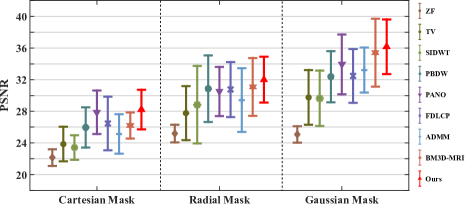

First, we test on 25 T1-weighted MRI data using three different undersampling patterns with a fixed 10% sampling rate. Fig. 3 shows the quantitative results (PSNR). Our method performances best for all three cases and has stronger stability compared with the second best method on variance. As for the effect of sampling ratios variation, we use radial mask under 10%, 30% and 50% sampling rates with evaluation of RLNE and MSE. Fig. 4 shows that our method has the lowest reconstruction error for all sampling rates. For more intuitive comparison, we illustrate the reconstruction error in term of pixels in Fig. 5. We also offer the qualitative comparison in Fig. 6. Visualized results demonstrate our method has better performance in both artifacts removing and details restoration. Time consuming is also considered. We compare our method with others on the 25 T1-weighted data using Radial mask with 10% and 50% sampling rate. Notice that ADMM-Net and ours are tested on GPU for the incorporation of deep architecture. Tab. 1 shows that our method provides an efficient reconstruction process and comes to the fastest method among the state-of-the-art competitors.